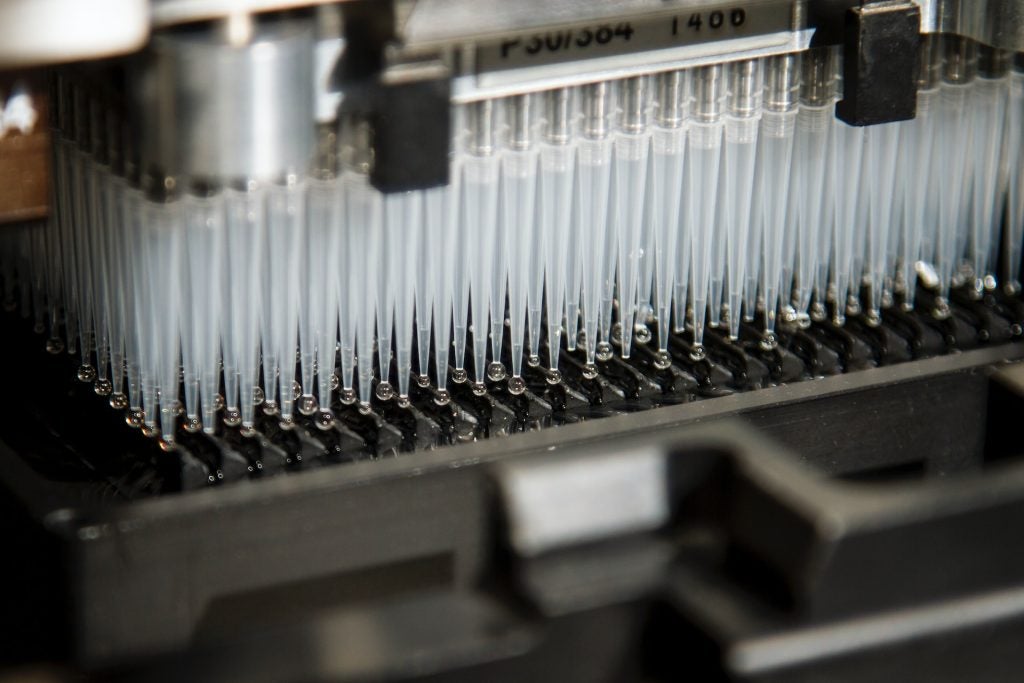

Researchers use AI to develop syringe for injecting proteins into human cells

DeepMind’s AI programme, AlphaFold, can predict three-dimensional structures of protein.